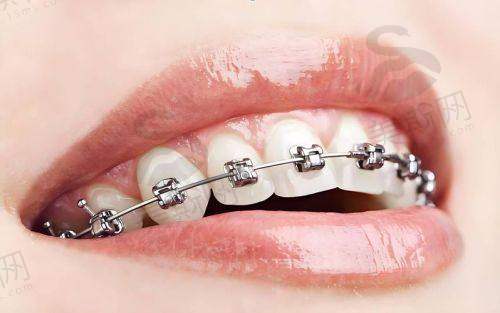

2. 数字化舌侧矫治精细控制

作为国内首批开展舌侧矫正的骨干医生,他研发的“个性化舌侧托槽系统”通过3D打印技术定制托槽角度,使矫治力作用点更接近牙阻抗中 心,在压前牙内收、上颌扩弓等方面成效提升40%。临床实例显示,骨性凸嘴患者采用舌侧矫正 + 颌位调整技术,18 - 24个月可实现侧貌从凸面型到直面型的转变,复发率低于2%。